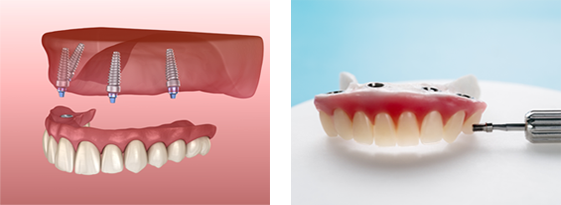

OSCAR All-on-X 임플란트

기존 틀니에 디지털을 더한 전악 회복 프로젝트!

OSCAR All-on-X 임플란트란?

오스카55플란트치과 OSCAR All-on-4 임플란트는

적은 식립으로 전체 임플란트가 가능합니다.

치아가 하나도 없는 경우에도 4개의

소수 임플란트를 식립하여 전체 치아를 수복합니다.

틀니처럼 빼고 끼지 않아도 되서

내 치아같이 사용하실 수 있습니다.

소수 임플란트 식립 (4개)

탈착하지 않아도 되는 편리함

경제적인 비용

오스카55플란트치과는 무치악 환자의 틀니 스캔부터

플래닝, 가이드 제작, 시술, 최종 보철에 이르는

전 과정을 FULL DIGITAL 디지털화 하여 정밀함을 높였습니다.